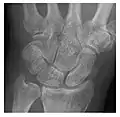

High-energy trauma fractures

Occult osseous injuries may result from a direct blow to the bone by compressive forces of adjacent bones against one another or by traction forces during an avulsion injury. Lesions in the tibial plateau, hip, ankle, and wrist are often missed. In a tibial plateau fracture, any disruption of the posterior and anterior cortical rims of the plateau should be sought. Impaction of subchondral bone will appear as an increased sclerosis of the subchondral bone (Figure 1). In the hip, posterior acetabular fractures also present subtle radiographic findings. The acetabular lines should then be carefully examined keeping in mind that the posterior rim, which is harder to see on X-rays, is more frequently fractured than the anterior rim (Figure 2). In the wrist, detection of carpal bone fractures is often challenging, with up to 18% of scaphoid fractures radiographically occult. Carpal fractures, especially the scaphoid, are associated with the risk of avascular necrosis. In apparently normal wrist radiographs from symptomatic patients, if there is history of a fall on an outstretched hand with pain in the anatomic snuffbox, suggesting scaphoid injury, the initial examination with posteroanterior, lateral, and pronation oblique views must be complemented by other specific views such as supination oblique and the "scaphoid" view A careful examination of cortices for evidence of discontinuity or offset and cancellous bone for lucency is necessary (Figure 3).[1]

a

b

c

Figure 3: A 26-year-old man presenting with wrist pain after being assaulted. (a) Initial anteroposterior radiograph shows a subtle linear lucency within the scaphoid extending to the scaphocapitate articular surface that was overlooked (arrow). (b) Initial "scaphoid" view was negative. (c) Followup anteroposterior radiographs, 12 days later, shows obvious scaphoid fracture (arrows).[1]